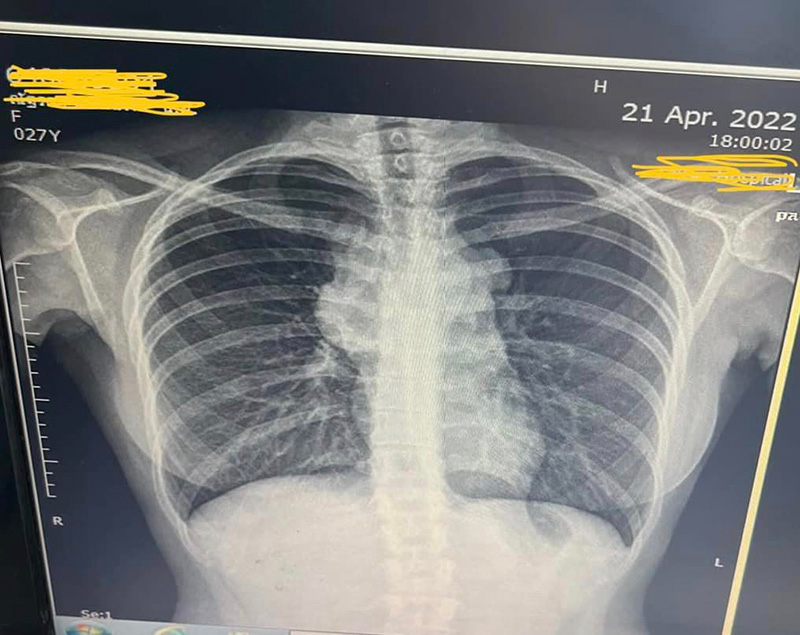

วันที่ 25 กุมภาพันธ์ 2566 เพจเฟซบุ๊ก พักก้อน ของ หมอลูกหนู ซึ่งโพสต์แชร์ประสบการณ์รับมือกับมะเร็งต่อมน้ำเหลือง ในวัย 27 ปี แม้ที่ผ่านมาจะใช้ชีวิตแบบระมัดระวัง ไม่กินเหล้า ไม่สูบบุหรี่ ไม่เที่ยวกลางคืนก็ตาม โดยหลังจากตรวจพบมะเร็ง ส่งผลให้ต้องพักงานและรักษาตัวด้วยเคมีบำบัดกว่า 6 เดือน จนปัจจุบันมะเร็งอยู่ในสถานะโรคสงบ (in remission) ก่อนจะได้กลับไปทำงานรักษาคนไข้อีกครั้ง